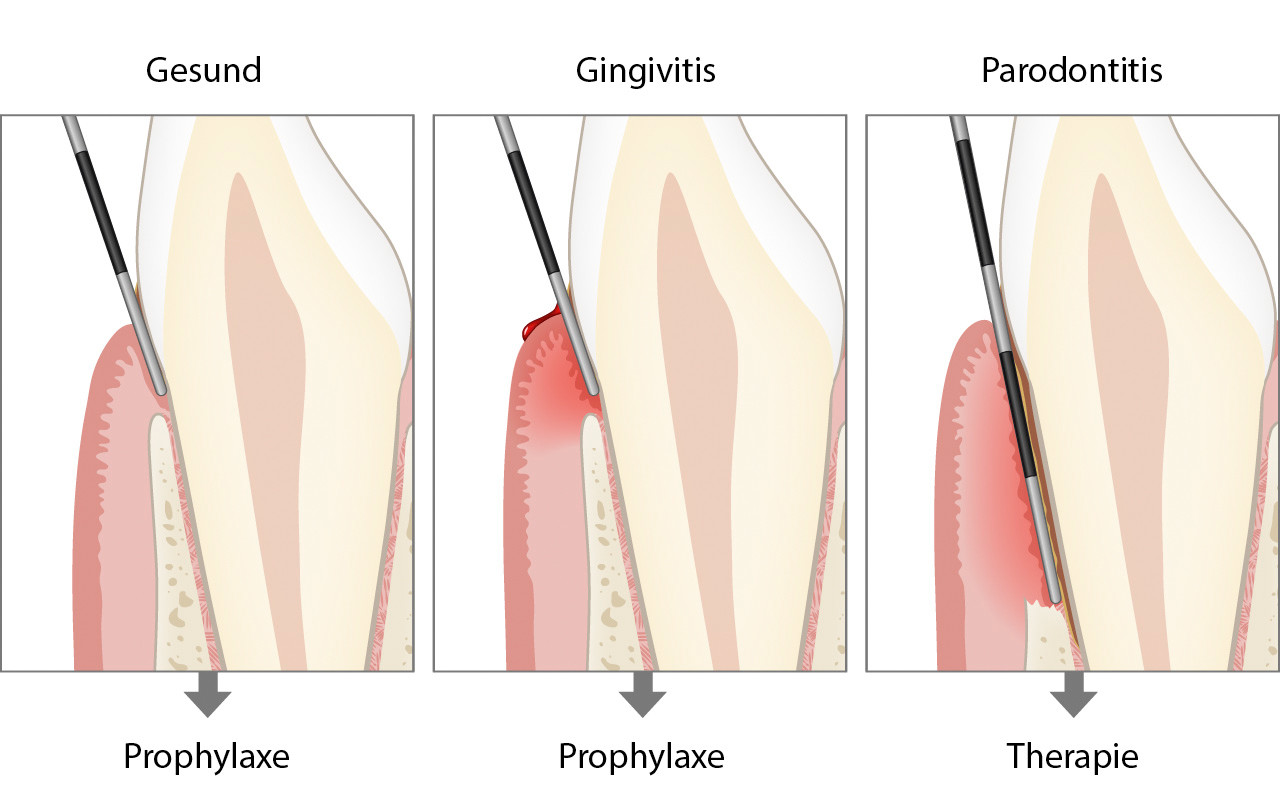

Erst die korrekte klinische Untersuchung in der Zahnarztpraxis mit einer sogenannten Zahnfleischsonde (Parodontalsonde) kann Aufschluss geben, ob das Zahnfleisch gesund ist, eine Zahnfleischentzündung (Gingivitis) oder bereits eine Erkrankung der Zahnverankerung (Parodontitis) vorliegt.

Parodontale Grunduntersuchung

Bei einer ersten Kontrolle kann der Zahnarzt oder die Dentalhygienikerin eine sogenannte parodontale Kurzuntersuchung durchführen, die nur wenige Minuten dauern wird.

Mit der parodontalen Grunduntersuchung soll in kurzer Zeit festgestellt werden, ob Zahnfleischprobleme vorhanden sind. Es kann dabei auf einfache Weise eine Gingivitis bestimmt oder eine Parodontitis aufgedeckt werden.

Mit einer Zahnfleischsonde (Parodontalsonde) wird an ausgewählten Stellen schonungsvoll und millimetergenau die Eindringtiefe am Zahnfleischrand gemessen.

Nach dieser Kurzuntersuchung werden weitere Abklärungen nur dann durchgeführt, wenn dabei Zeichen für den Abbau der Zahnverankerung gefunden wurden. Diese Abklärungen beinhalten den sogenannten Parodontalstatus sowie zusätzliche Röntgenbilder.